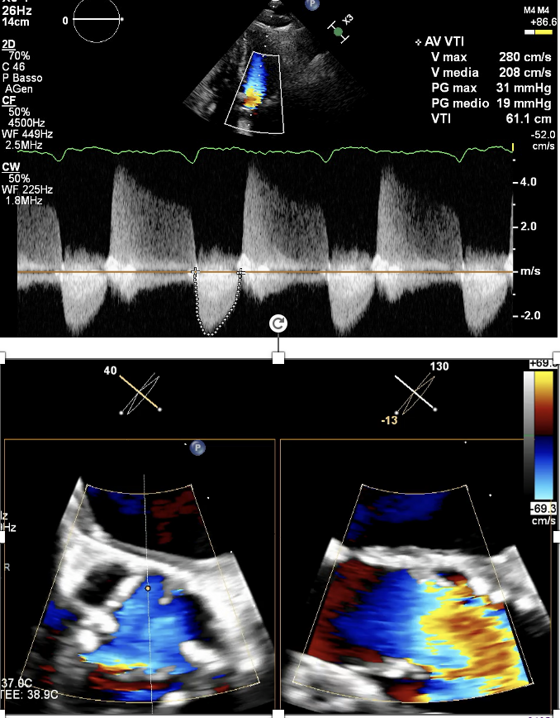

la diagnosi viene fatta con un esame non invasivo e indolore, l'ecocardiografia color-Doppler.Per completare le indagini, viene anche eseguita una tac del cuore e degli accessi vascolari per valutare la fattibilità di interventi non invasivi e escludere patologie concomitanti